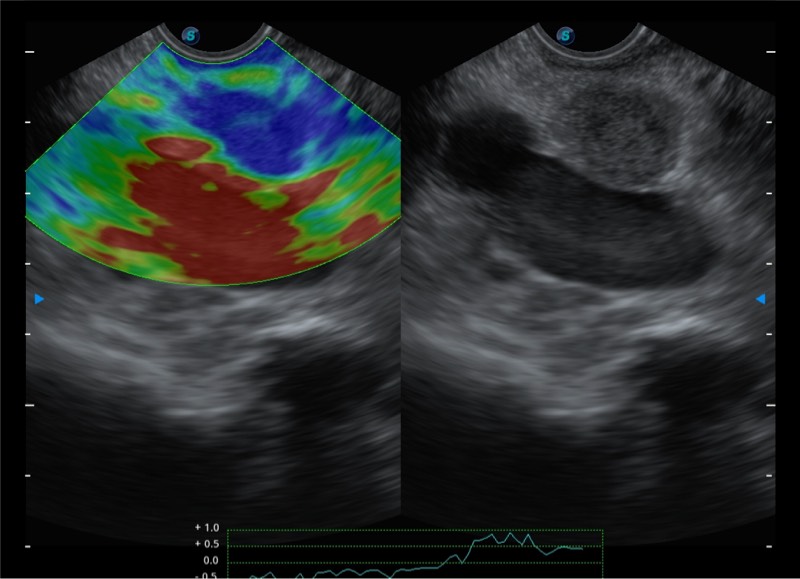

基于二十年的超声技术积累,环球UG官网提供了最新一代的独立超声主机,在提供高质量图像的同时满足多学科使用。具备常见多普勒技术并提供弹性成像、声学造影等高端影像技术。新一代传感器具有更强的抗干扰能力并减少图像伪影。

150°超声扫描角度

4-12MHZ宽频输出